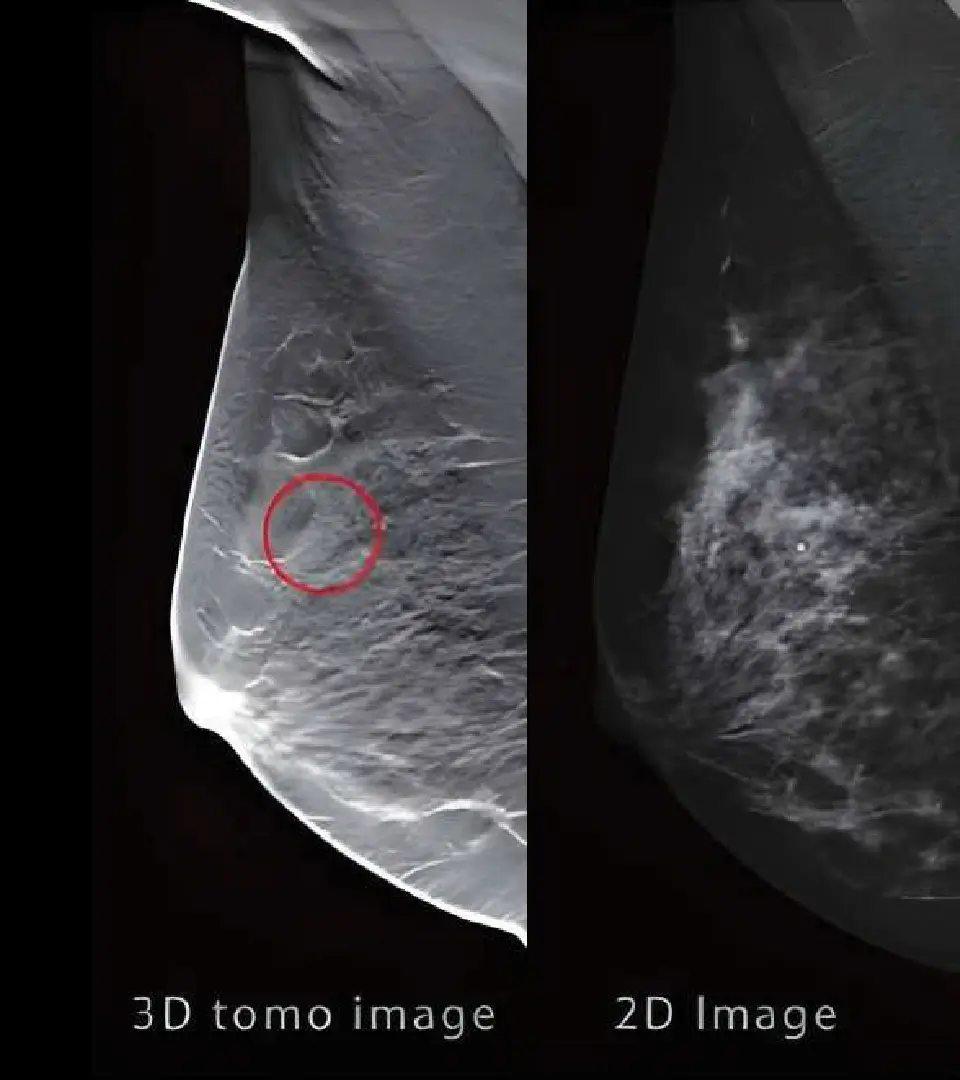

Equipo de Mastografía: Garantizando la Detección Temprana y la Seguridad de tus Pacientes